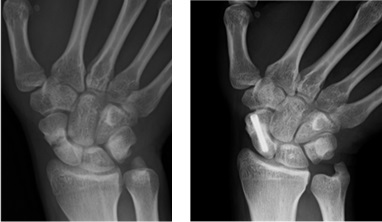

TFCC損傷

外傷、手関節の使いすぎ、年齢的な変化により手関節を回旋(ひねる動作)で手関節の特に小指側の痛みが生じる状態です。自分でひねるときにクリック音を来す人もいます。

治療方法

関西電力病院独自の縫合器具で鏡視下にTFCCの縫合が可能です。

縫合後は3週間上腕から指の根元までギプスを行いその後自動運動を3週間行います。術後6週間からリハビリを始めますが当院ではTFCCに手慣れた作業療法士(ハンドセラピー)の指導の下に行われます。リハビリとして平均約3ヶ月を要しています。(無理すると再断裂の恐れがあり、できるだけ当院の専門ハンドセラピーのもとリハビリを行うことをお勧めしています。)